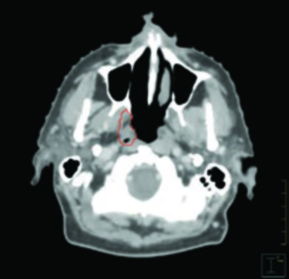

El caso de carcinoma amigdalino VPH-positivo cT2N0 tratado unilateralmente muestra cómo, incluso en el escenario de tratamiento ipsilateral, la cobertura se extiende superiormente hasta la lámina pterigoidea ipsilateral. La cobertura ganglionar inicia en la apófisis transversa de C1, abarcando la base de lengua y el paladar blando ipsilaterales sin cruzar la línea media.